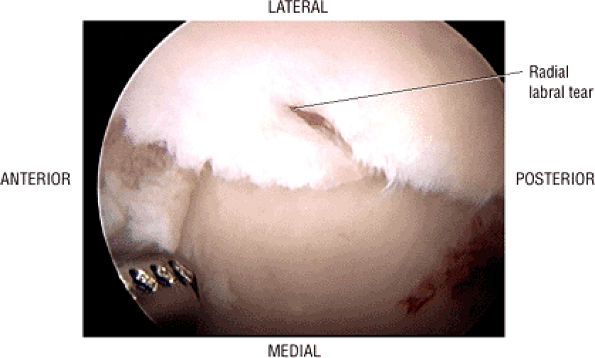

The acetabular notch and fat pad, loose bodies, synovial tissue, and notch osteophytes

The posterior labrum

-

The lateral labrum

The anterior labrum

Labral hypertrophy

Soft, blistered, or delaminated acetabular cartilage

Perilabral sulcus, cysts, spurring, and labral tears